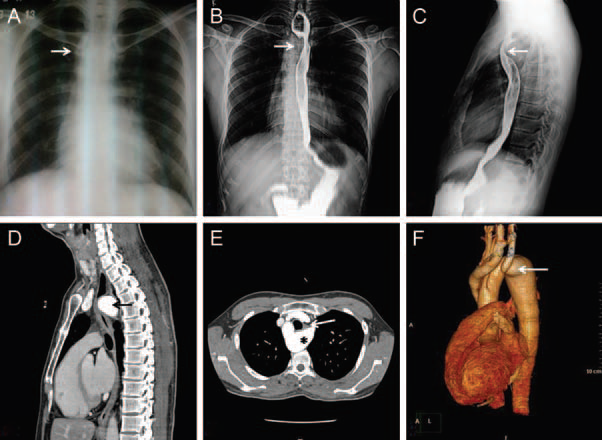

A 38-year-old male presented with history of atypical chest pain and dysphagia. Cardiovascular examination was unremarkable. Electrocardiography and transthoracic echocardiography were normal. Chest radiograph showed right-sided aortic arch (Panel A). Barium swallow was performed, which showed extrinsic compression from right side (Panel B) and from posterior aspect (Panel C) at the level of T4 vertebra. Computed tomography aortogram confirmed right-sided aortic arch with left-sided large aortic diverticulum extending posterior to the oesophagus with marked compression (Panel D and E). There was no compression of the trachea. The volume rendered reconstruction image showed anomalous origin of left common carotid from the ascending aorta and left subclavian artery originating from the diverticulum.

The patient underwent successful surgical resection of the diverticulum with reimplantation of the left subclavian artery to descending thoracic aorta. He made prompt recovery with dramatic improvement in dysphagia. Aortic arch anomalies should be ruled out in patients with dysphagia and right aortic arch irrespective of age at presentation. In individuals with suspected aortic arch anomalies, computed tomography imaging by providing an accurate anatomical diagnosis guides surgical decision-making.

Panel A Chest radiograph showing right-sided aortic arch (arrow). Panels B and C Barium swallow imaging showing extrinsic compression on right side (B) and on posterior aspect (C) of oesophagus (arrows). Panels D and E Computed tomography aortogram showing large aortic diverticula (asterisk) with retroesophageal extension causing marked compression on the oesophagus (arrow). (F) Computed tomography volume rendered aortography showing right-sided aortic arch with anomalous origin of left common carotid from ascending aorta and left subclavian artery arising from aortic diverticulum.